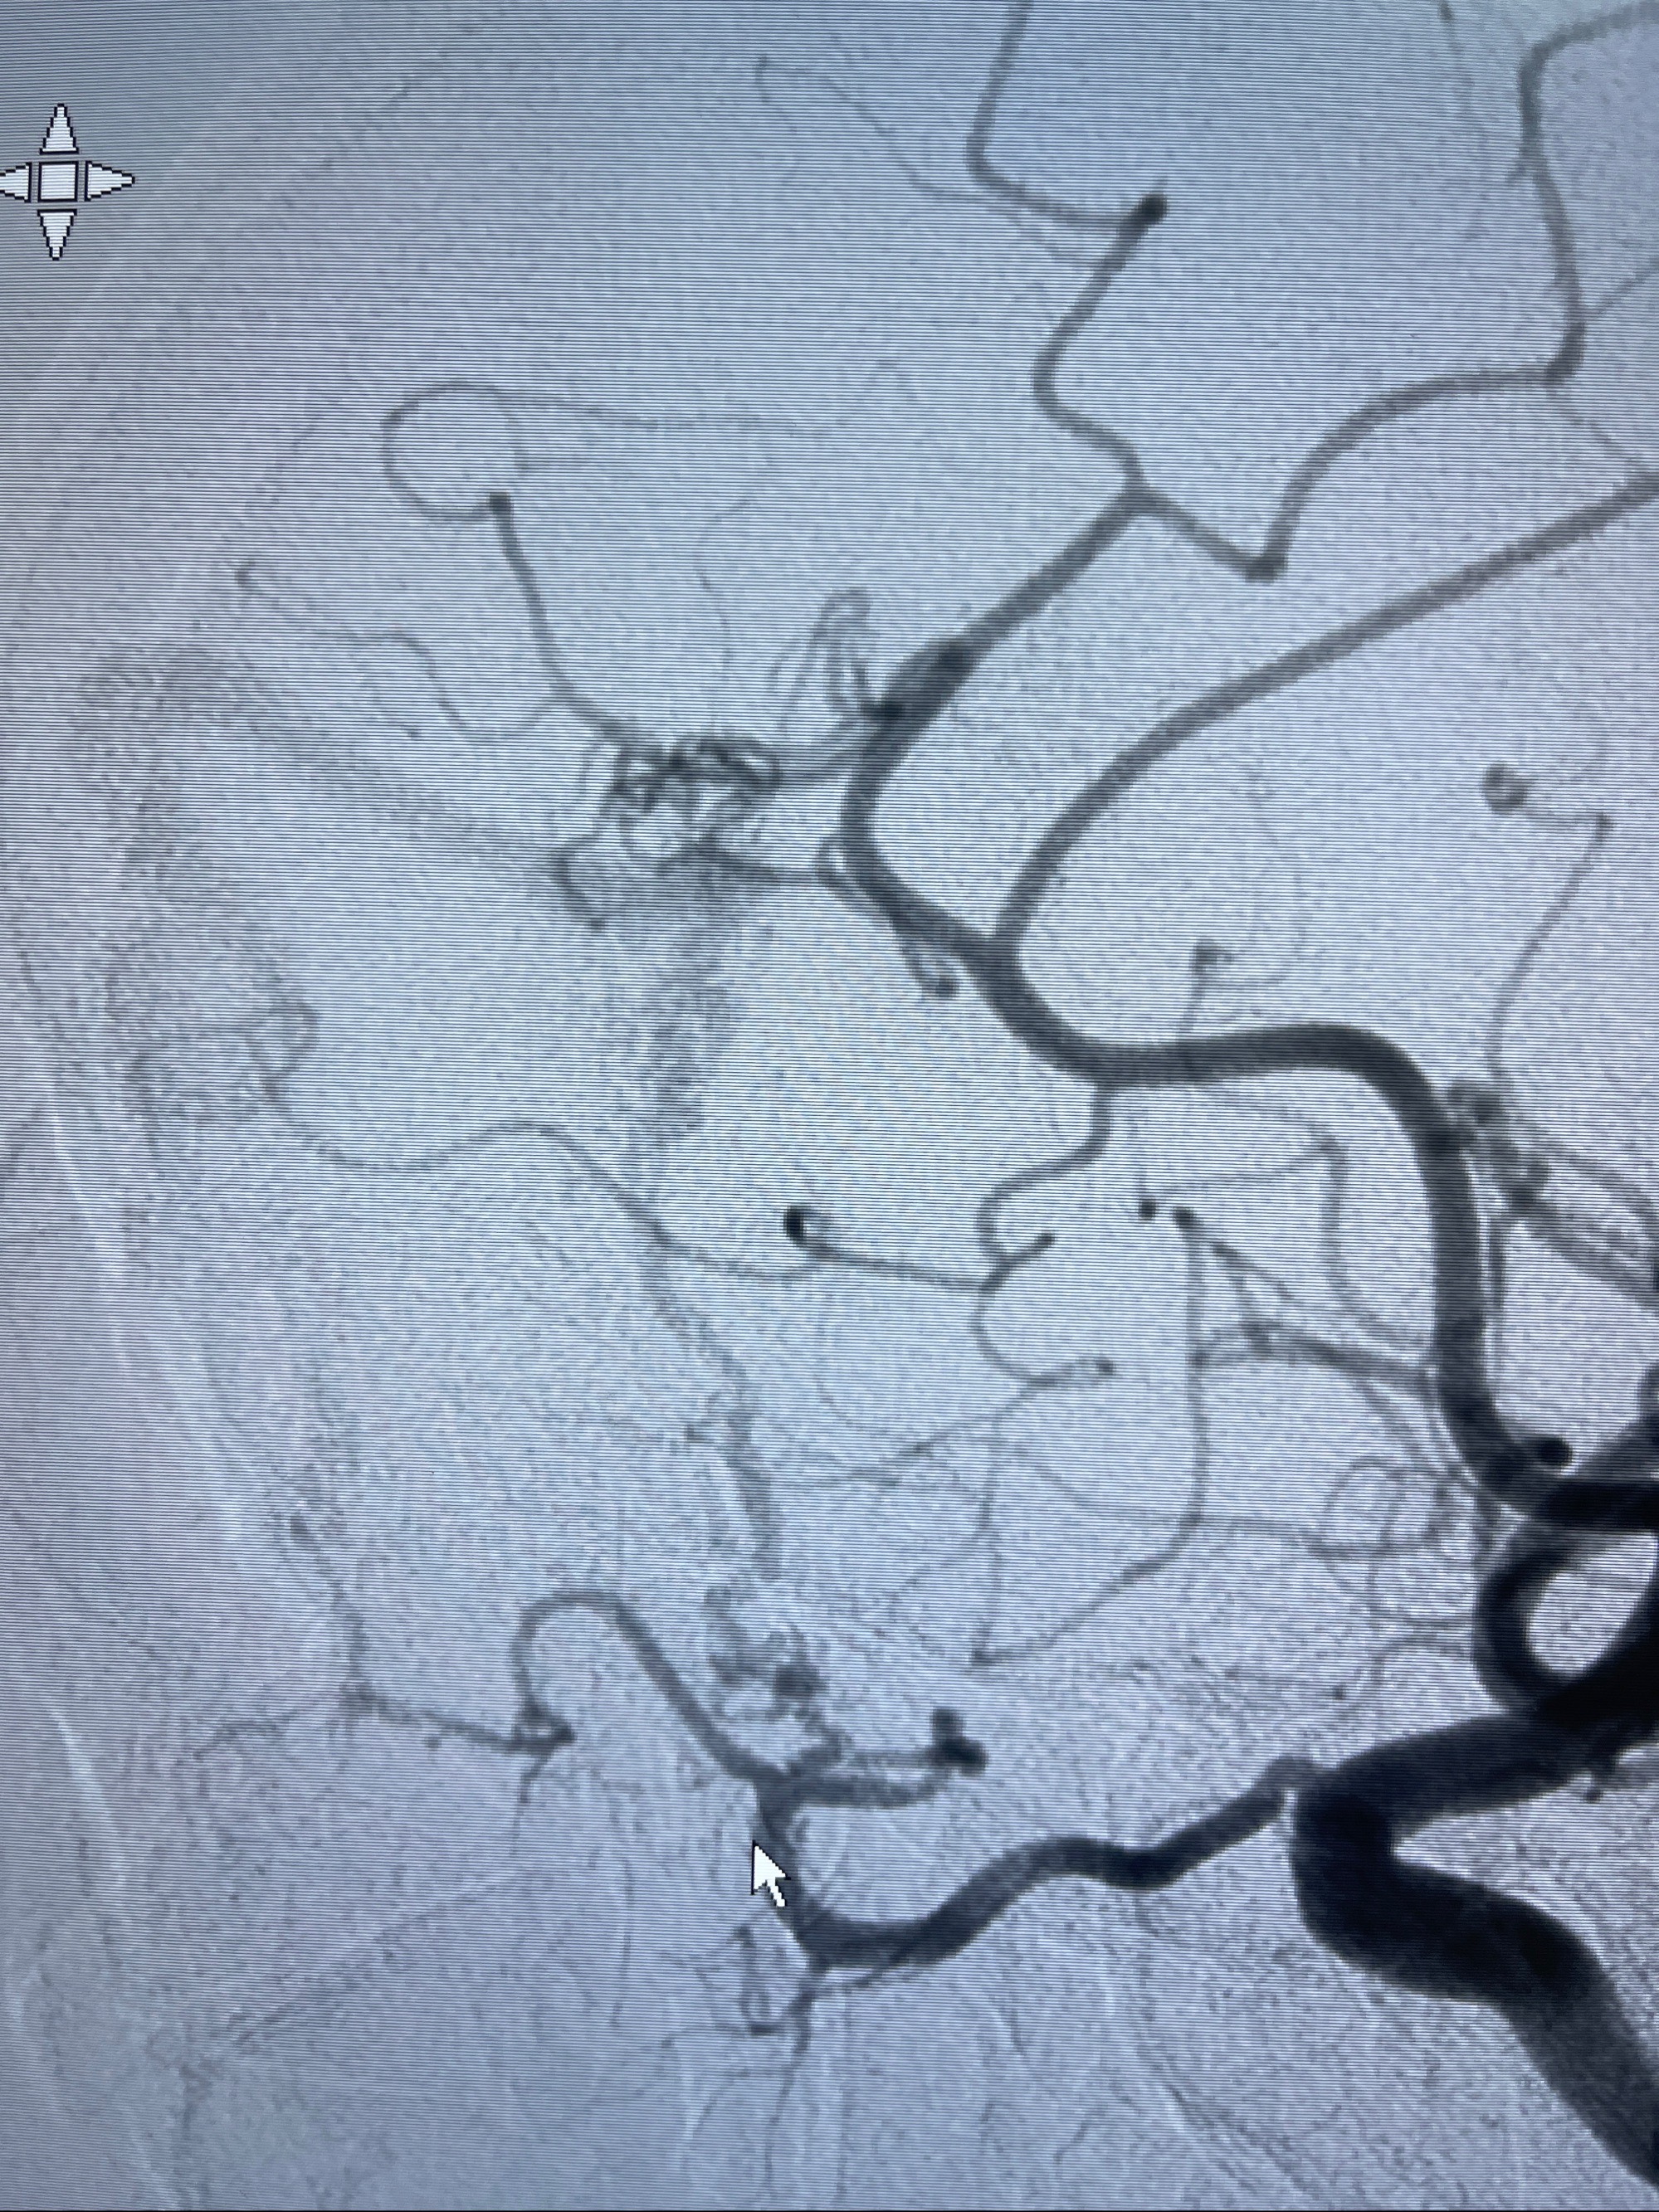

2023-09-13全脑血管造影:前颅底硬脑膜动静脉瘘,供血动脉为双侧胼周动脉、眼动脉脑膜支,静脉向上矢状窦方向引流

治疗策略:

- 外科手术?

- 介入干预:静脉途径栓塞or动脉途径填塞?